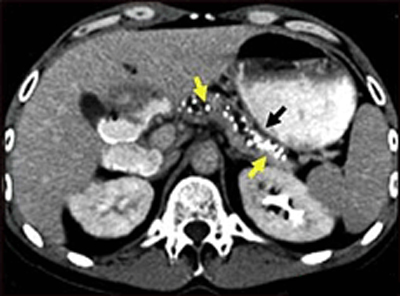

Çok sayıda beyaz renkli kalsifikasyon gösteren üst batın BT taraması. Bunlar kronik pankreatitte ortaya çıkar.

Abdominal BT veya MRI

Karın BT taraması veya MRI, safra yolları içindeki tıkanıklıkları da tanımlayabilir. Her iki tarama da safra kanalı görüntülerinin bir bilgisayar monitöründe gösterildiği invaziv olmayan prosedürlerdir.